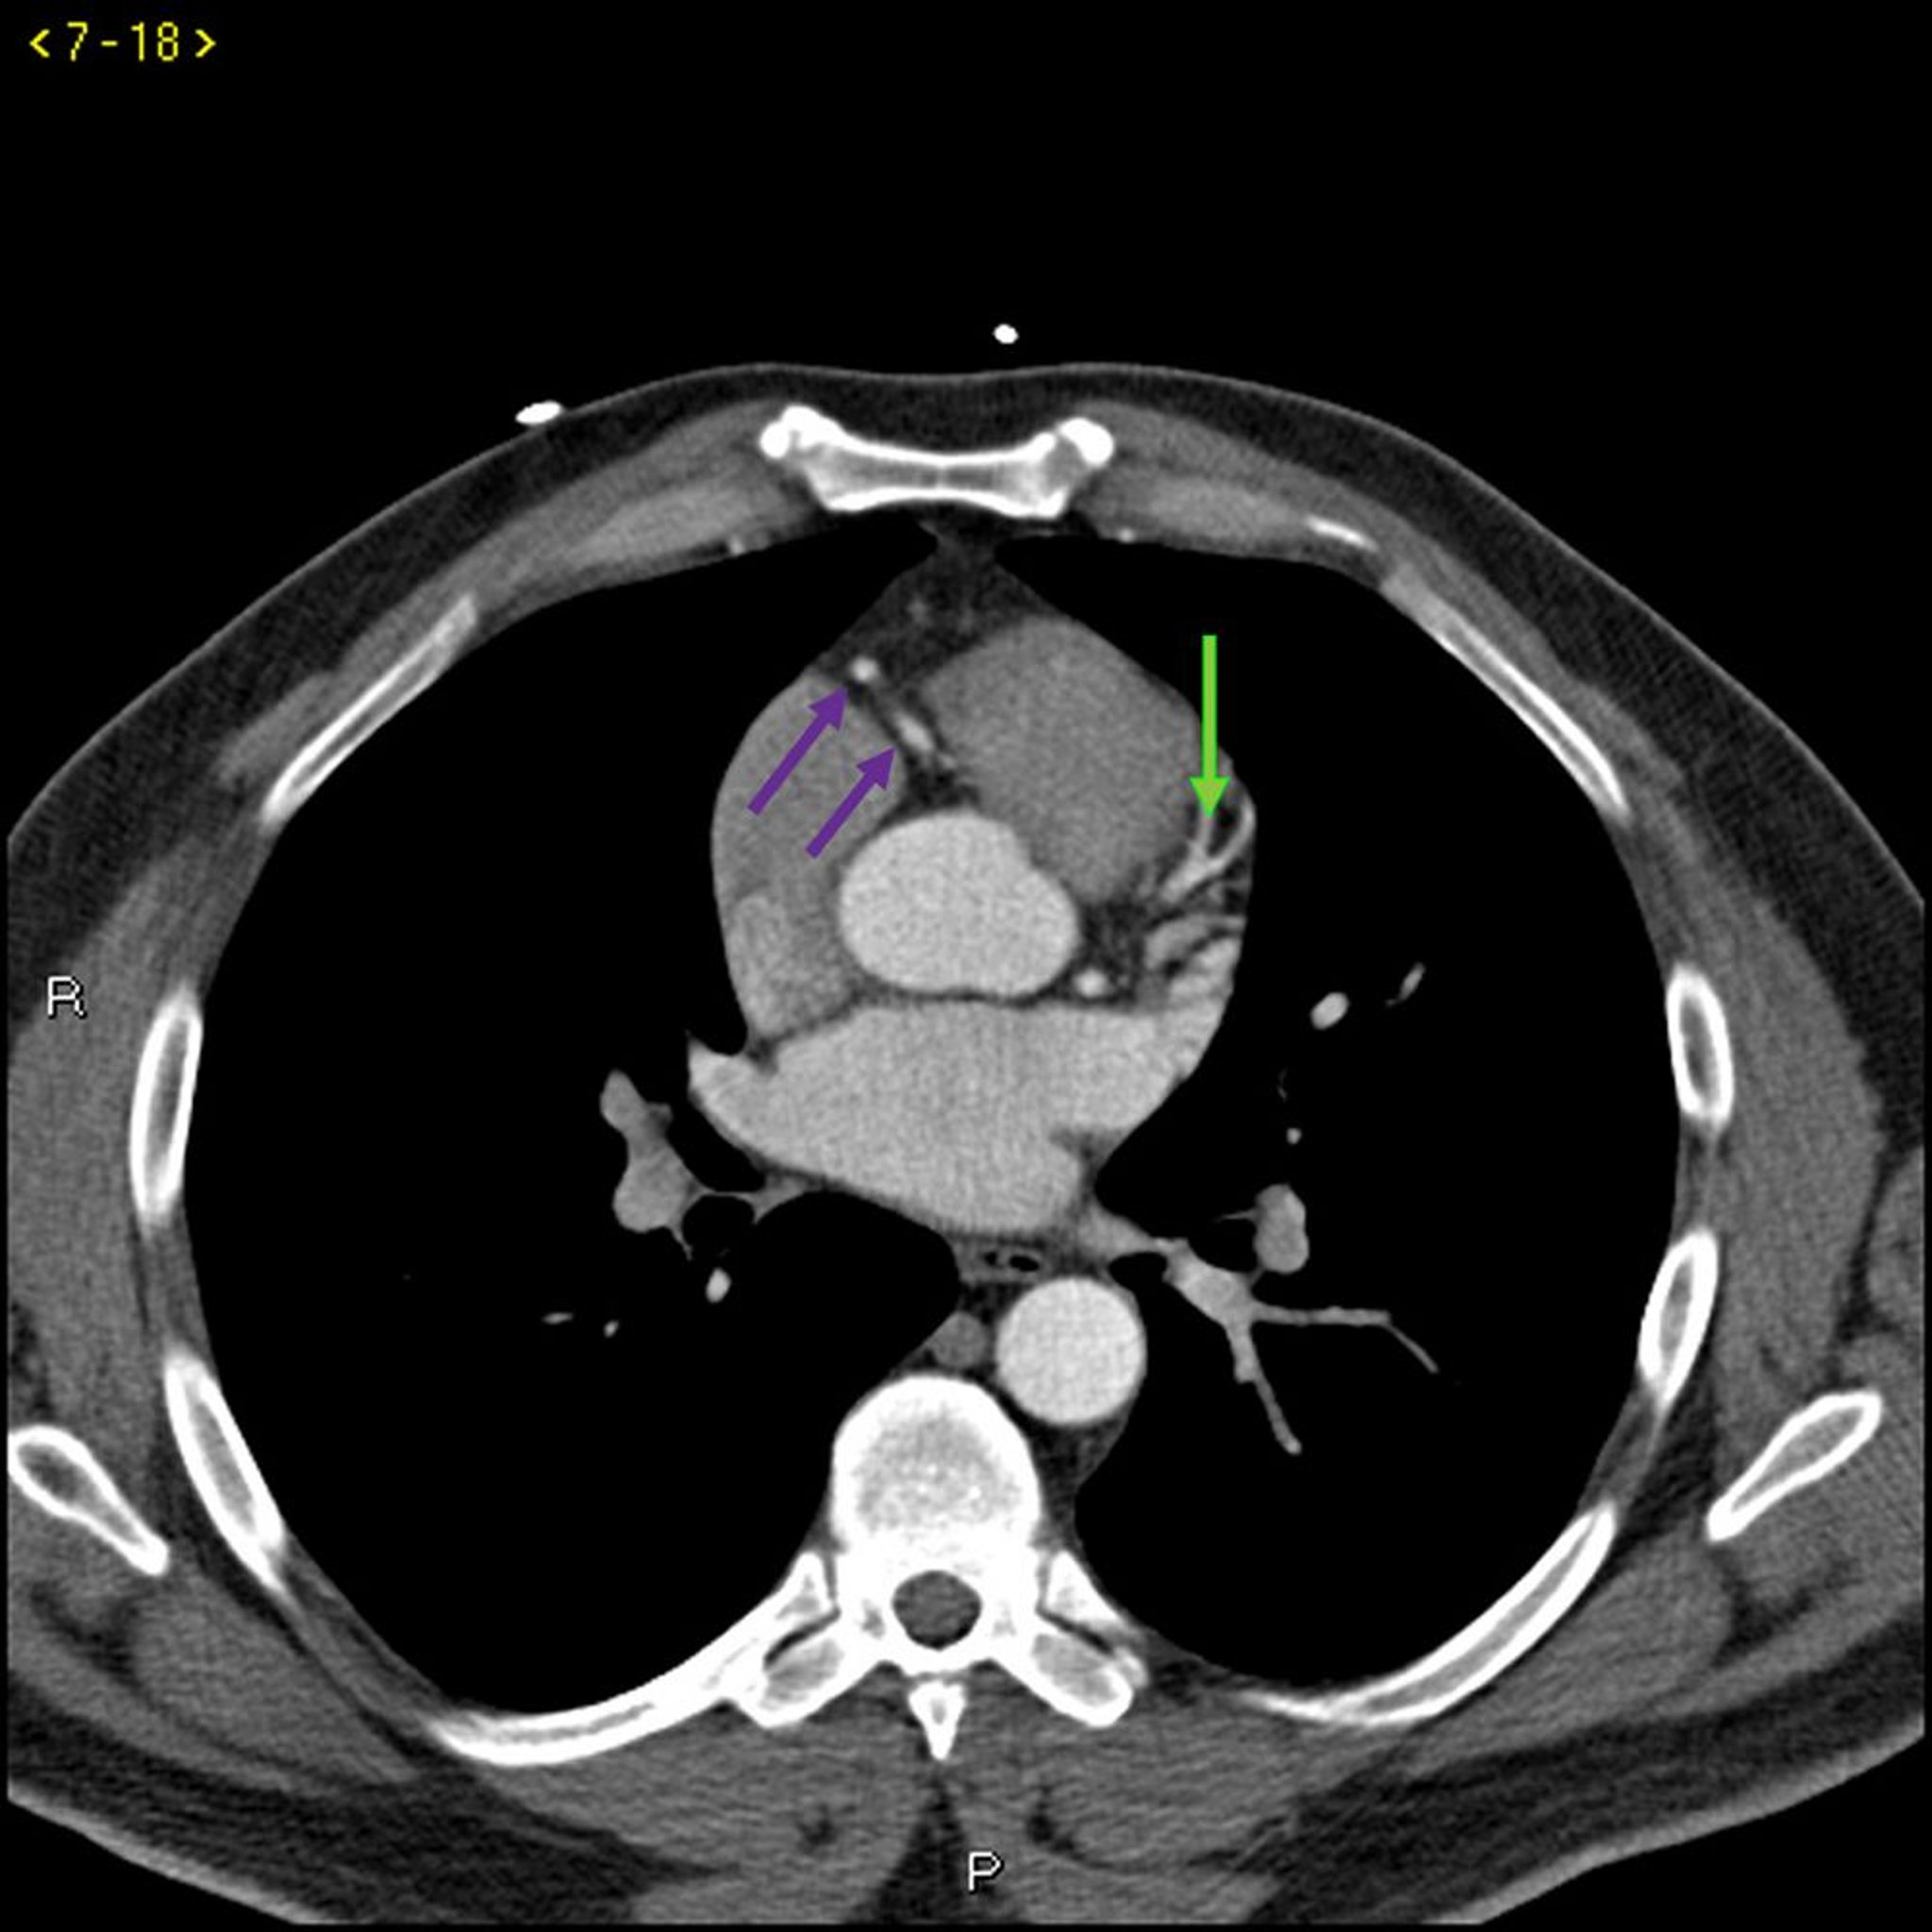

TDM avec contraste montrant des artères coronaires normales – Coupe 3

Cette TDM avec contraste montre des artères coronaires normales. Le tronc commun coronaire gauche est indiqué par la flèche rouge. Les artères interventriculaire antérieure gauche et circonflexe gauche sont indiquées par les flèches verte et bleue respectivement et l'artère coronaire droite est indiquée par la flèche violette.